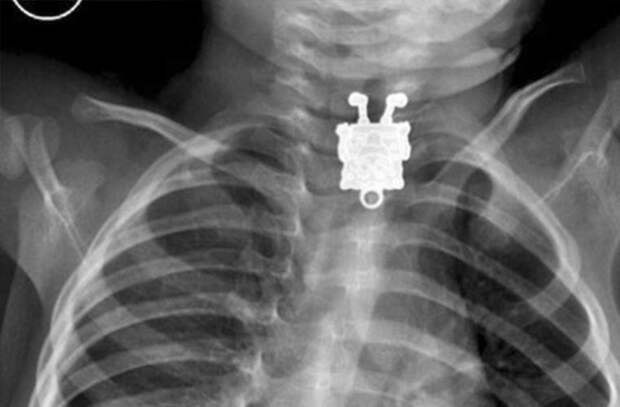

Рентген, на котором виден катетер, введенный доктором в свое тело

Вернер Форсман рассматривает рентгеновские снимки своего тела с катетером

Здесь и далее: инородные предметы внутри человека, рентген